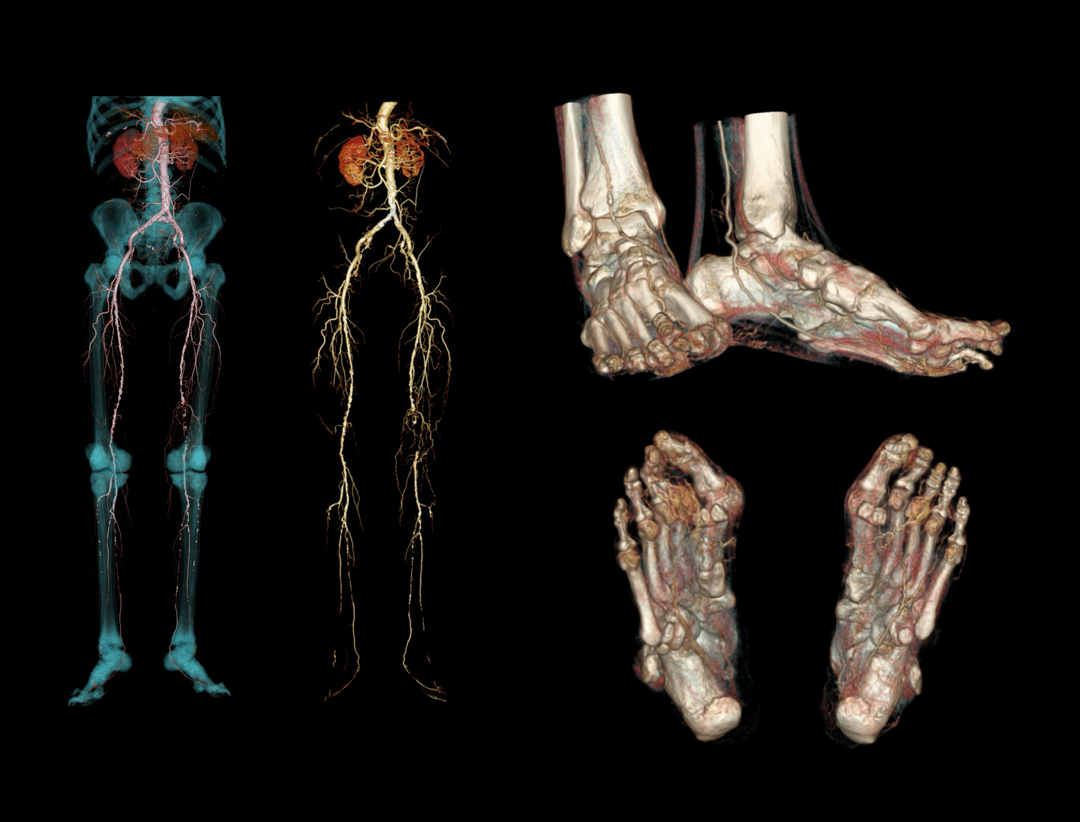

Run-off CTA